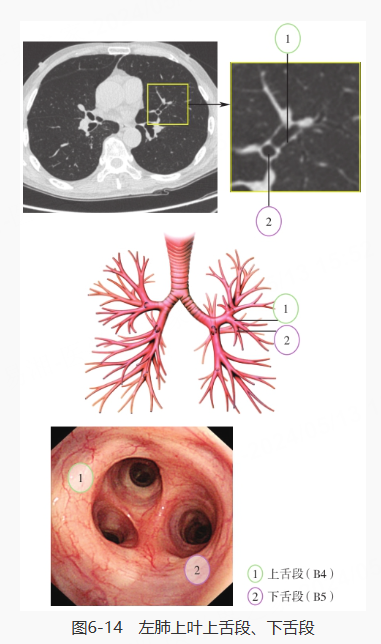

再对左肺进行探查,分别是左主支气管、左肺上叶·下叶、左肺上叶上支·舌支、左肺上叶尖后段·前段、左肺上叶上舌段·下舌段、左肺下叶、左肺下叶背段、左肺下叶基底段: